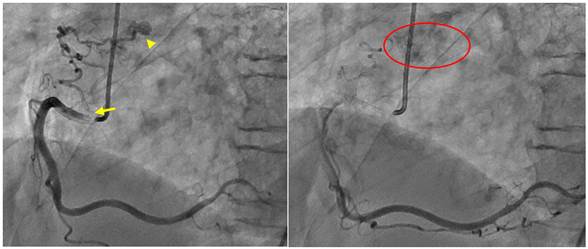

- arteriografía coronaria que evidencia tronco coronario común corto sin lesiones, ADA de mediano calibre y largo recorrido hasta ápex sin lesiones significativas. Se visualizó una fistula coronario-pulmonar en segmento medio de ADA (Figura 1). La ACD de buen calibre sin lesiones, observando una fístula hacia arteria pulmonar en su segmento proximal (Figura 2). En ninguno de los dos casos, se encontró alteración del flujo coronario de forma distal. La arteria circunfleja de buen calibre, sin lesiones. Dichos hallazgos posiblemente sean de origen congénito sin repercusión hemodinámica y que no estaban en relación a la sintomatología de paciente.

Figura 2: A) Arteriografía selectiva a ACD. Se visualiza el inicio (flecha) y porción final (cabeza de flecha) de la fístula desde segmento proximal de ACD. B) Se visualiza contraste en arteria pulmonar (círculo rojo).